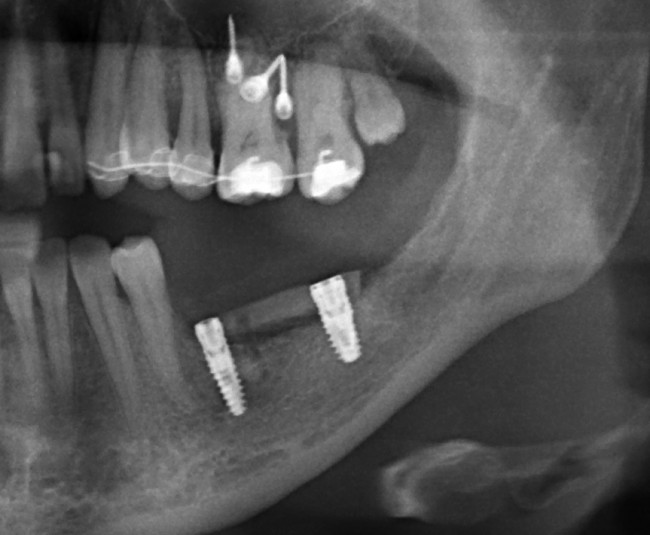

Итак, вот изначальная ситуация:

до лечения

Я понимаю, что данных на части панорамного снимка очень мало для правильной интерпретации клинической ситуации, но, с другой стороны, это позволит не перегрузить Вас информацией.

Дано:

• боковой сегмент, отсутствуют три зуба: 35, 36, 37. Эти зубы удалены достаточно давно, развилась сильная атрофия костной ткани.

• верхние зубы, не имея антагонистов, выдвинулись вниз (зубоальвеолярное удлинение, т. н. «симптом Попова-Годона»).

• пациентке примерно 30 лет. То есть, вся жизнь еще впереди)).